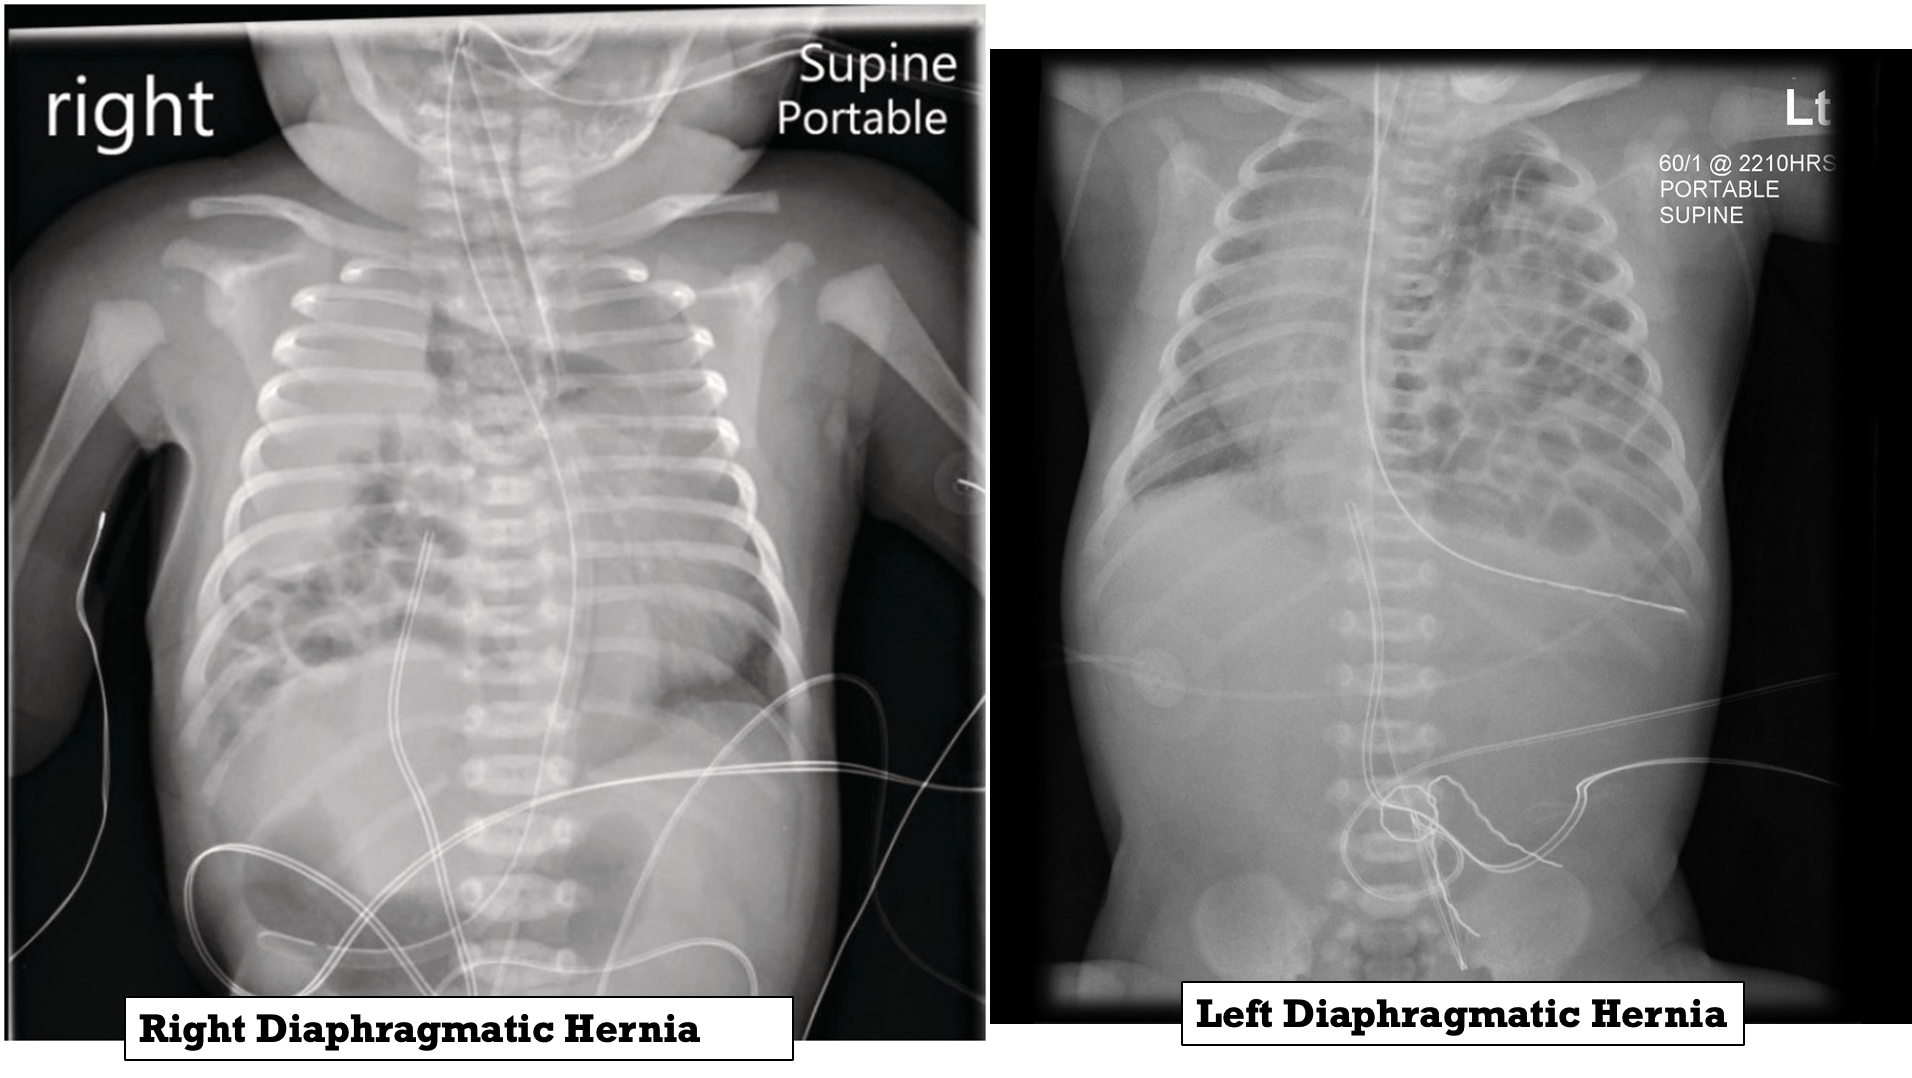

Diaphragmatic Hernia

Occurs when the diaphragm fails to completely close during development, allowing for abdominal contents to enter the chest cavity. 85% occur on the left side and 15% occur on the right side.

The ipsilateral lung is hypoplastic, and there will be a contralateral shift of the mediastinum, resulting in contralateral lung hypoplasia.

- Chest radiography: to confirm diagnosis of congenital diaphragmatic hernia

The diagnosis is made or confirmed by radiograph.